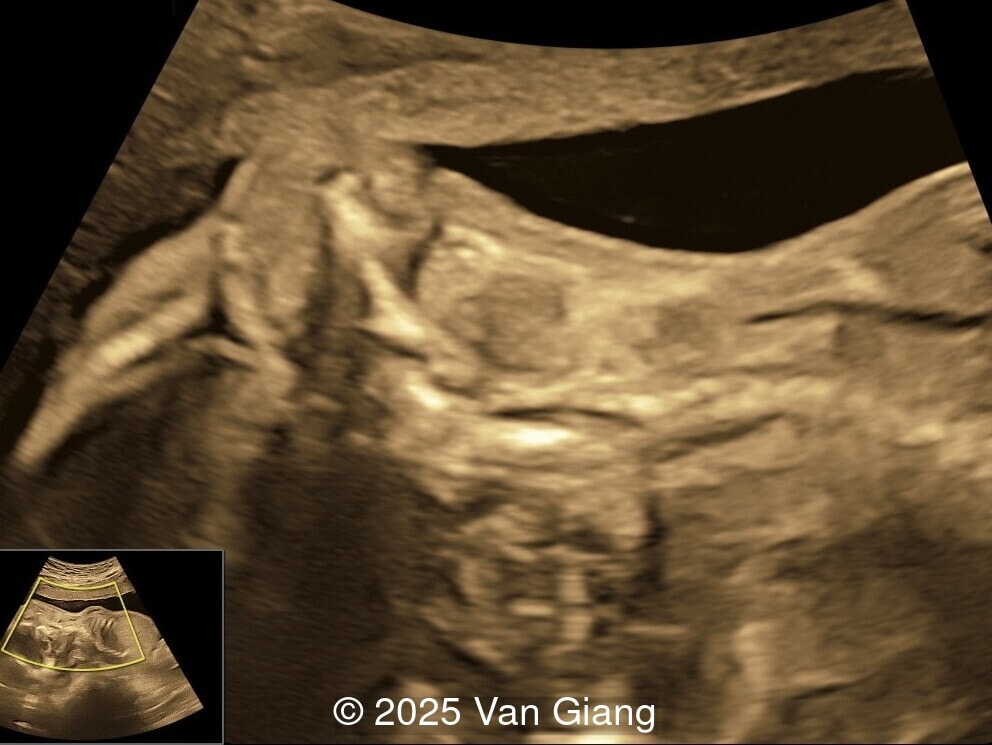

A 32-year-old primigravida presents at 20 weeks gestation without first trimester screening. Ultrasound reveals a small for gestational age fetus with the following anomalies:

Image 2

Ultrasound revealed severe mandibular and zygomatic hypoplasia, glossoptosis, cleft palate, and micrognathia with an abnormal facial profile. Both upper limbs showed radial ray sequence with abnormal thumbs and shortened forearms. Unilateral clubfoot was also noted. No major cardiac or visceral anomalies were observed. Based on these findings, Nager syndrome was suspected.